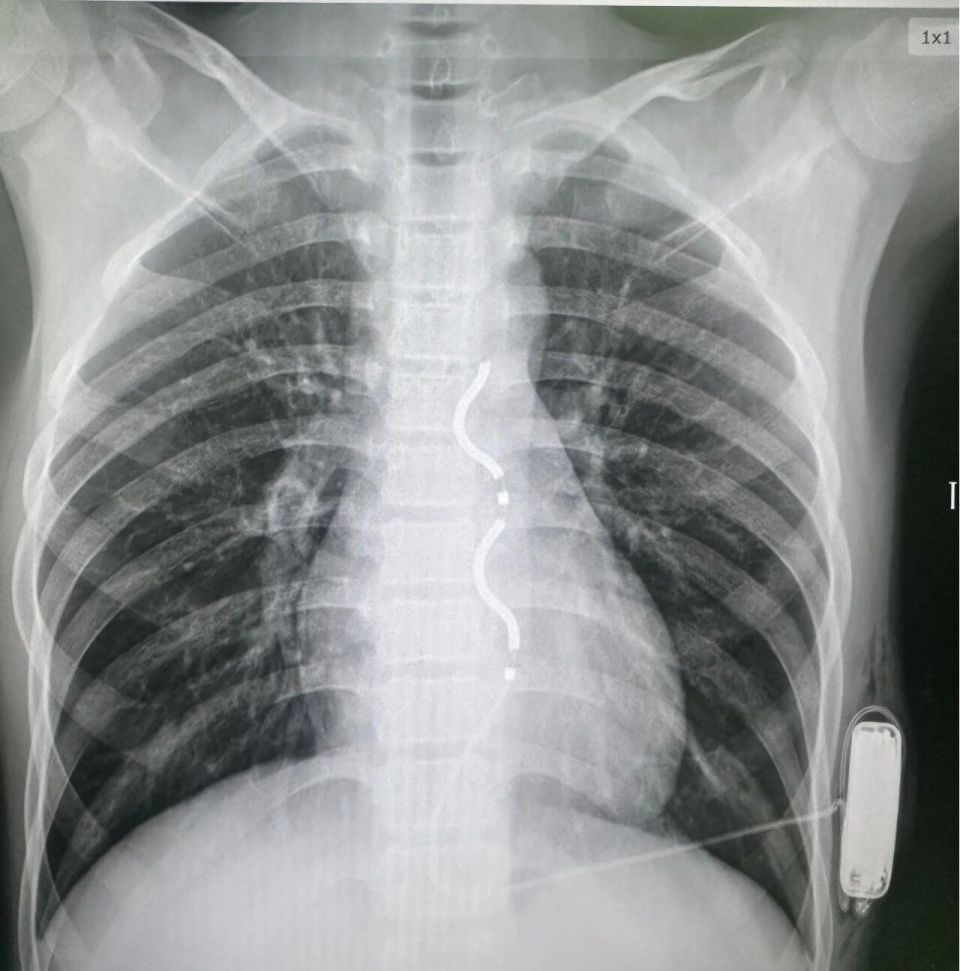

EV-ICD影像

手术当日,在心脏外科、麻醉科的紧密配合下进行,石琳精心安排手术步骤,江河副主任凭借精湛的技术,精准地将除颤电极导线沿胸骨旁皮下隧道放置到预定位置,并在患儿左侧胸壁皮下制作囊袋放置ICD脉冲发生器。整个手术过程顺利,术中测试显示除颤系统感知良好,除颤功能有效,成功为患儿的心脏安装了“体外守护神”。

面对患儿危急的病情和有限的治疗选择,术前心内科组织MDT多学科会诊进行了深入细致的评估。团队最终决定为患儿实施EV-ICD植入术。这是一种最尖端的植入式除颤技术。与传统经静脉路径及皮下路径不同,EV-ICD系统将除颤电极导线埋藏于胸骨与心脏之间前纵隔,不进入心血管腔内。技术优势较传统ICD显著:1.完全避免了经静脉植入可能导致的心脏瓣膜损伤、血管穿孔、血管内导线感染等严重并发症;2.保留了完整的静脉通路,为患儿未来可能的其他心脏治疗(如起搏、消融)留有余地;3.更适合处于生长发育期的儿童,减少了因身高增长导致导线张力过高或移位等问题;4.除颤成功率高,耗电量小,除颤器使用寿命更长。